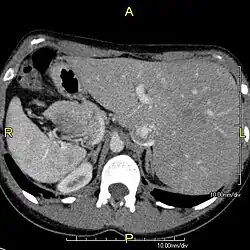

Diagnosis of situs inversus can be made using imaging techniques such as x-ray, ultrasound, CT scan, and magnetic resonance imaging (MRI).[9]

The condition affects all major structures within the thorax and abdomen. Generally, the organs are simply transposed through the sagittal plane. The heart is located on the right side of the thorax, the stomach and spleen on the right side of the abdomen and the liver and gall bladder on the left side. The heart's normal right atrium occurs on the left, and the left atrium is on the right. The lung anatomy is reversed and the left lung has three lobes while the right lung has two lobes. The intestines and other internal structures are also reversed from the normal, and the blood vessels, nerves, and lymphatics are also transposed.

If the heart is swapped to the right side of the thorax, it is known as "situs inversus with dextrocardia" or "situs inversus totalis". If the heart remains on the normal left side of the thorax, a much rarer condition (1 in 2,000,000 of the general population), it is known as "situs inversus with levocardia" or "situs inversus incompletus".